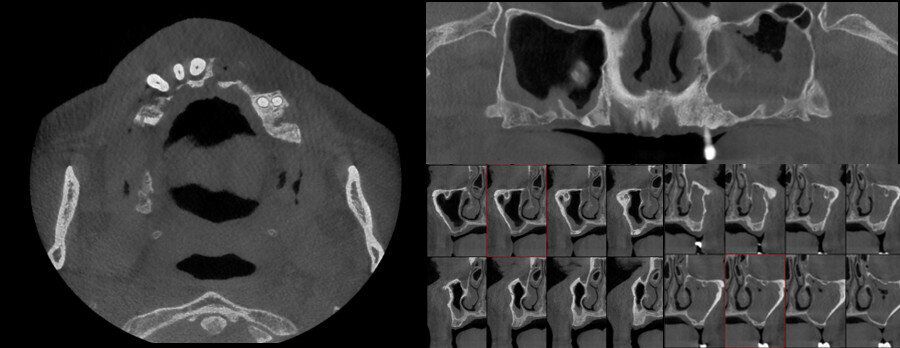

To complete the preoperative evaluation, a high-definition CT scan was performed, which revealed an extremely resorbed maxilla in the posterior. Placement of two zygomatic implants in the posterior and four conventional implants in the anterior sector of the maxilla was indicated (Fig. 3). The CT scan was uploaded to StealthStation S8, and matching between the patient’s actual anatomy and imaging was performed. The flat emitter was placed below the patient’s head to eliminate obstructions for pinless and surgical workflows (Fig. 4).

Figs. 3a–c: Initial CT scan with cross-sectional (a), coronal (b) and sagittal (c) views.